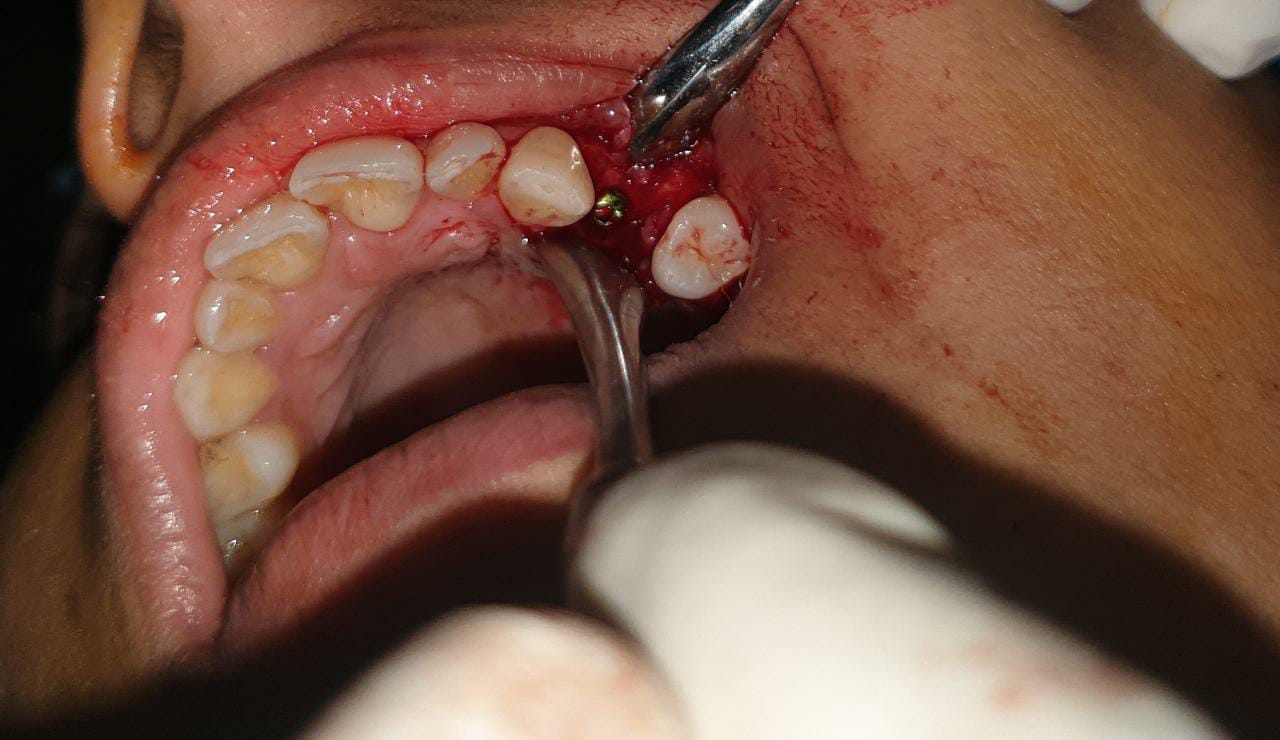

2.4 Live Surgical Demo Of Implant Placement

2.5 Implant Placement

2.6 Implant Placement

2.7 Implant Placement

2.8 Implant Placement

2.9 Implant Placement